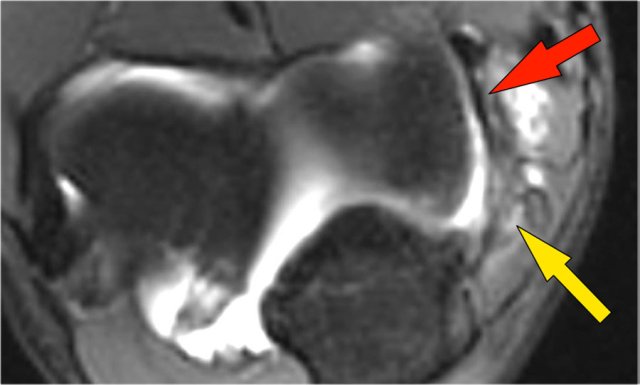

Arthrosis in valgus overload syndrome

Due to the valgus overload there are shear forces on the posteromedial part of the humeroulnar joint.

Notice the subchondral sclerosis seen on the T1W-image (red arrow).

On the T2W-image there is subchondral bone marrow edema and cartilage loss (yellow arrow).

These are images of a 20 year old baseball pitcher.

Scroll through the images.